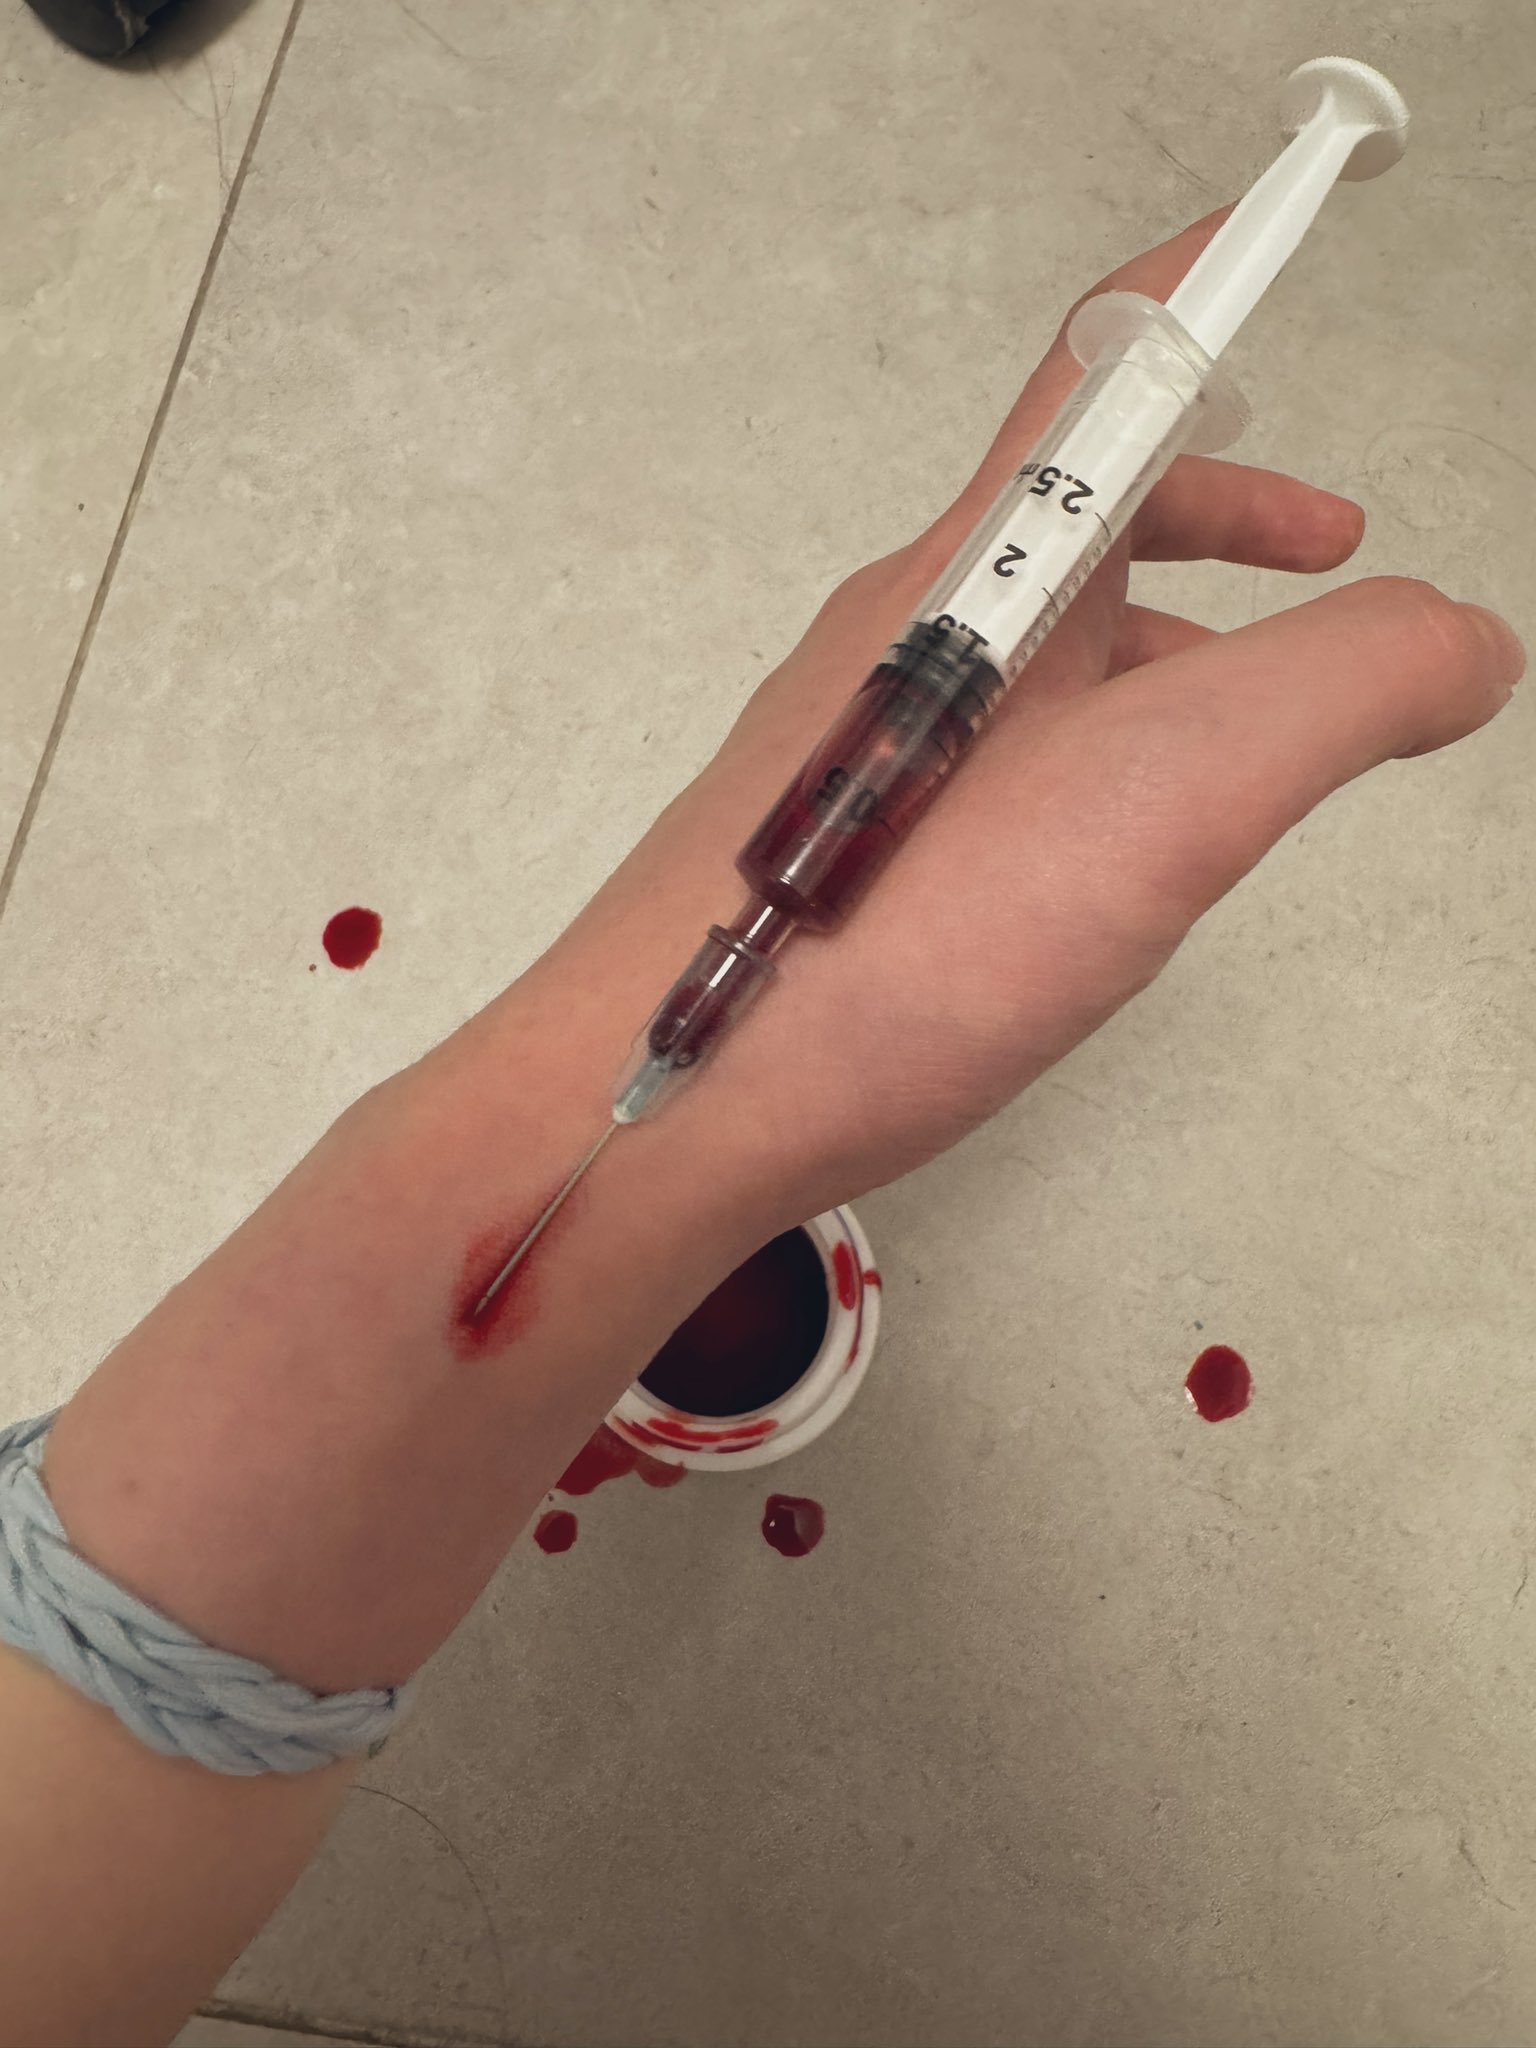

吃完唑吡坦会干一些难绷的事情,昨天睡不着疑似气急败坏了抽了0.5ml右美托咪定就是iv,还奇奇怪怪挑了个很痛的头静脉

后面不记得了,醒了灯开着的还以为是做梦,对着针孔一脸不可置信地整理记忆

你别说还扎得挺好的()按压时间估计也够,一点淤青也没有,不知道哪来的意志力 https://t.co/KxtfAUVSmb

TEST FROPOFOL

果然蝴蝶针会翻车,太难用了。

最后用了留置针,推2ml.

本来是1ml,但忘记关闸血液回流,我怕把针管堵了于是又推了1ml

*我竟然无师自通留置针了!用的肘静脉因为其他地方被蝴蝶针霍霍了

提前推了利多卡因(也是测试倒抽)所以毫无痛感,耶

配合另一种麻醉就可以无痛重开了(bushi) https://t.co/Uj139Q2tBk

炽烈已极 @AnIncandescence竟然能在50mg下撑那么久,意志力比我想的还要强大,但是乱七八糟。

手上都是血迹不说,周围的其他地方也有我意料之外的血迹